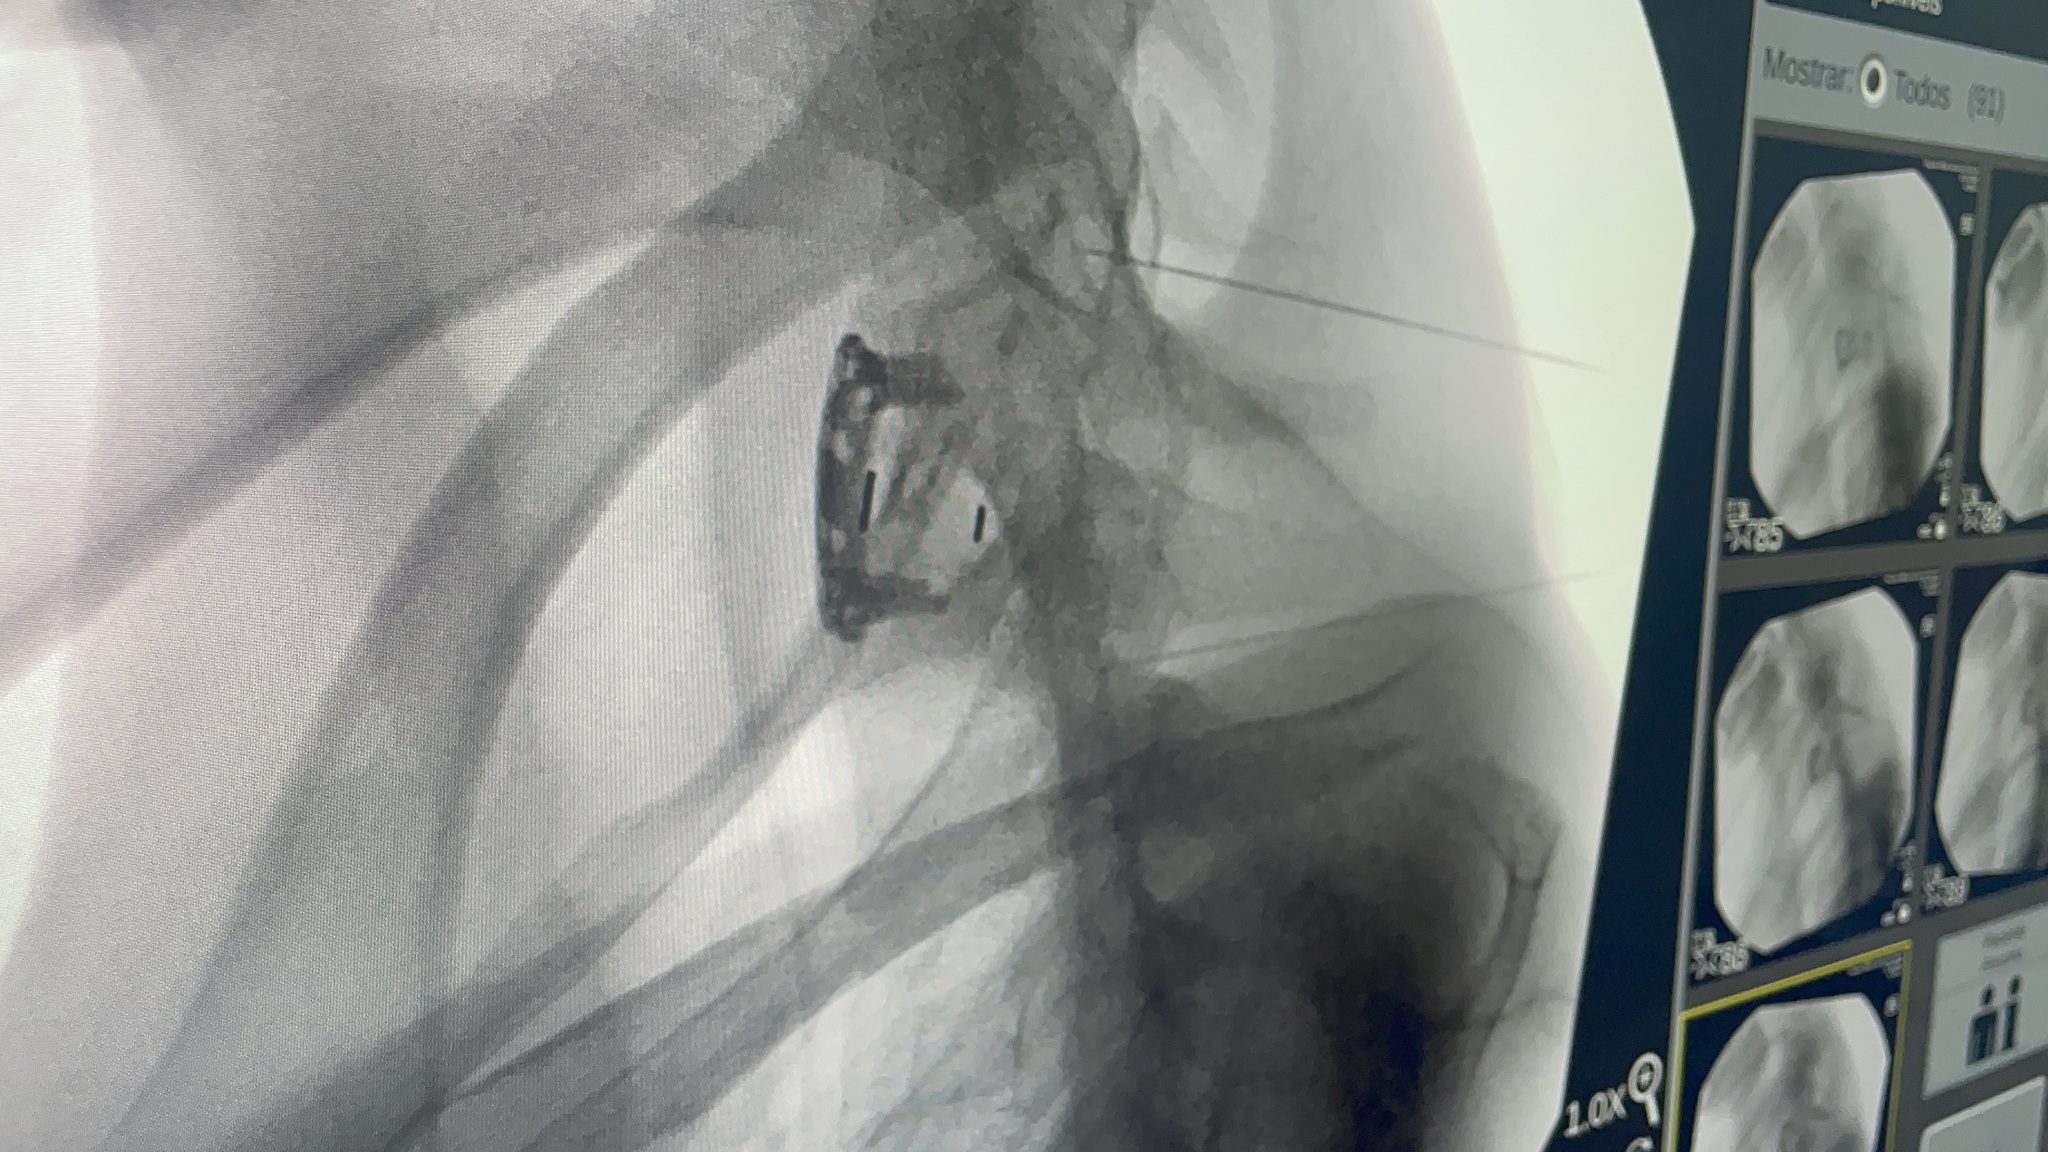

Operado na manhã desta quarta-feira (21) com a aplicação do medicamento experimental polilaminina, um militar tetraplégico de Dourados poderá recuperar os primeiros movimentos pouco a pouco, e apresentar melhora no quadro em aproximadamente um mês. A operação foi um sucesso, segundo a equipe responsável, e ele deverá receber alta amanhã (22).

Caso do militar - O paciente de Dourados tem apenas 19 anos e perdeu os movimentos após ser atingido por um tiro acidental no pescoço, no final de outubro do ano passado. Ele foi operado no Hospital Militar de Área de Campo Grande e foi o 13º paciente operado no Brasil por ordem judicial.

As melhores chances são nas situações em que a polilaminina é injetada na medula em até 72 horas após a pessoa sofrer a lesão, segundo divulgaram a equipe de pesquisadores e o laboratório Cristália, que desenvolve a droga em parceria com a universidade. No entanto, os estudos mostraram que há resultados em casos de lesões mais antigas, como é o caso do militar.